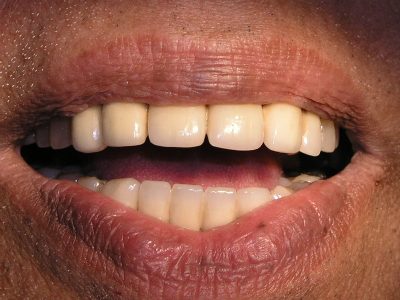

Old unpleasing crowns here were replaced with all Ceramic Crowns.